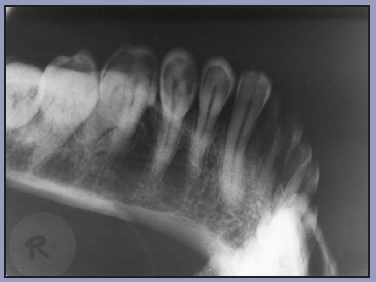

The purpose of the intraoral periapical examination is to obtain a view of the entire tooth and its surrounding structures, as in Figure 1. Two exposure techniques may be employed for periapical radiography: the paralleling technique and the bisecting angle technique. The paralleling technique is the preferred method. This technique provides less image distortion and reduces excess radiation to the patient. The paralleling technique should always be attempted before other techniques. The bisecting technique can be employed for patients unable to accommodate the positioning of the paralleling technique. Candidates may include those with low palatal vaults and children. Disadvantages to the bisecting technique include image distortion and excess radiation due to increased angulations involving the eye and thyroid glands. Regardless of the technique, however, the rules of radiography referred to earlier must be followed.

Figure 1 – Periapical Image

Figure 1